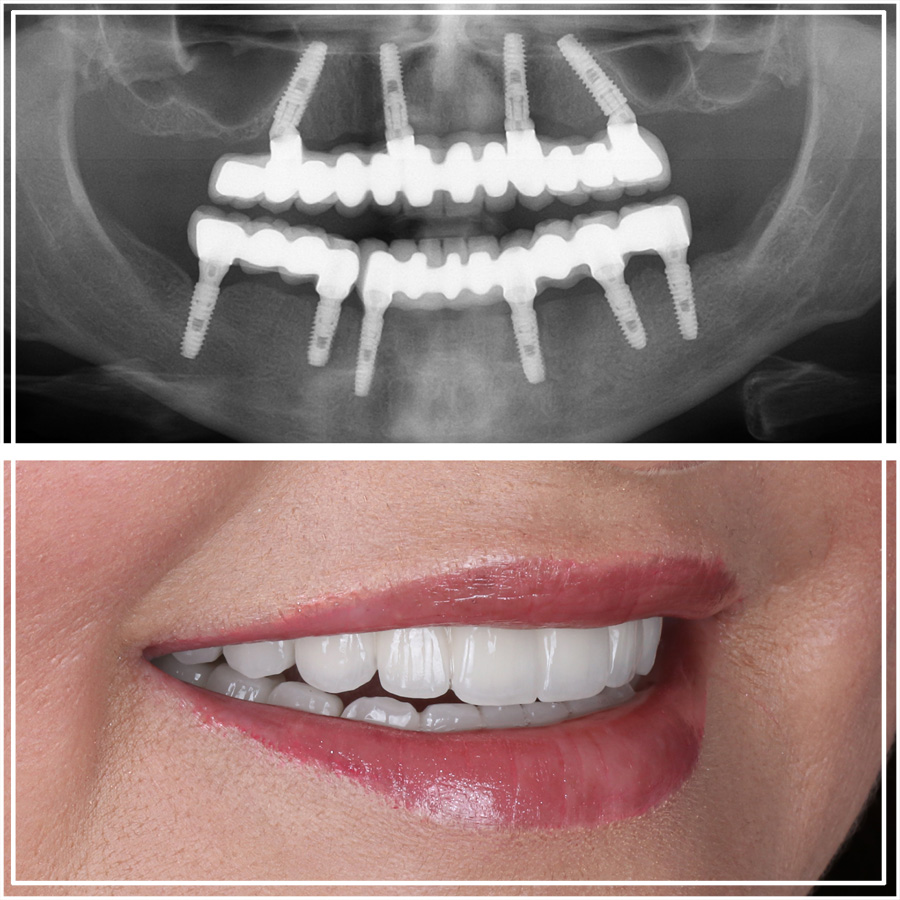

After 3 to 4 months of healing, the permanent bridge is fitted. Our “After” photos showcase:

Perfectly aligned “Hollywood” or “Natural-Look” smiles.

Gingival Matching: We use “pink porcelain” to mimic natural gum tissue, making the transition between the bridge and your mouth invisible.